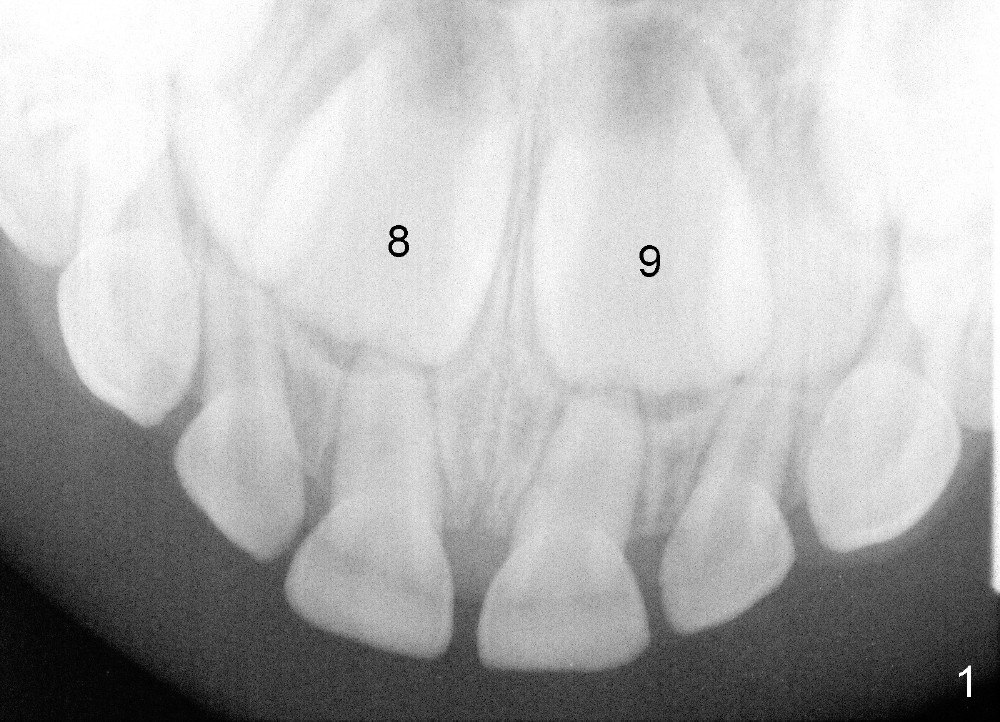

Now Devon is 7.5 years old. There is diastema between the centrals (Fig.9). #9 is in cross bite (Fig.10,11), while the lower incisors are crowded.

现在Devon七岁半,中切牙之间缝隙大(图九至十一:8,9),乳侧切牙已经脱落,但是没有足够间隙让恒侧切牙(图九:7, 10(C, H:乳尖牙))萌出,左上中切牙反合(图十:9),下切牙拥挤。